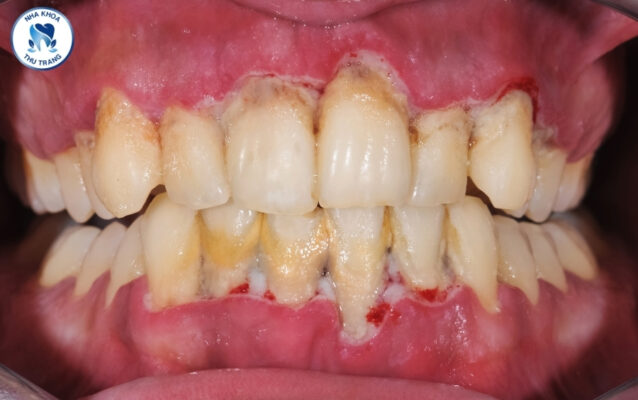

Viêm nha chu là gì?

2. Biểu hiện của bệnh nha chu

• Nướu sưng, chảy máu dù không có tác động nào

• Lợi có màu đỏ hoặc tím nhạt

• Đau khi chạm vào nướu

• Hiện tượng nướu tụt vào khiến răng trông dài ra so với bình thường

• Hôi miệng

• Răng lung lay

• Có mủ xuất hiện giữa răng và nướu răng

• Chảy máu khi đánh răngXEM THÊM: Sau khi thực hiện niềng răng có đau không?